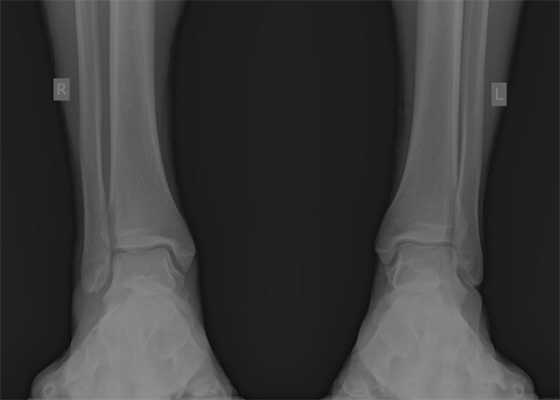

При детальном изучении снимков определяется увеличение межберцовой щели до 7,5 мм, уменьшения зоны перекрытия большеберцовой и малоберцовой костей до 5 мм, отсутствие на стороне поражения перекрытия тени таранной кости и малоберцовой кости.

На рентгенограмме костей правого и левого голеностопных суставов в прямой проекциии, снимки стоя - справа определяются признаки повреждения дистального межберцового синдесмоза - степень взаимного перекрытия берцовых костей 5мм (в норме больше 6мм) увеличенное большеберцовое - малоберцовое пространство - 7.5мм (в норме до 6мм).